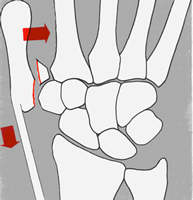

Der Sturz auf den gestreckten Daumen ist meist die

Ursache für diese Problemfraktur. Der Zug der Sehen verursacht

die Dislokation. Die geschlossene Reposition und Gipsfixation kann

die Frakturstellung nicht aufrechterhalten. Die Stabilisierung mit

Kirschnerdrähten, Schrauben oder am einfachsten mit dem Minifixateur

sind die Verfahren der Wahl.